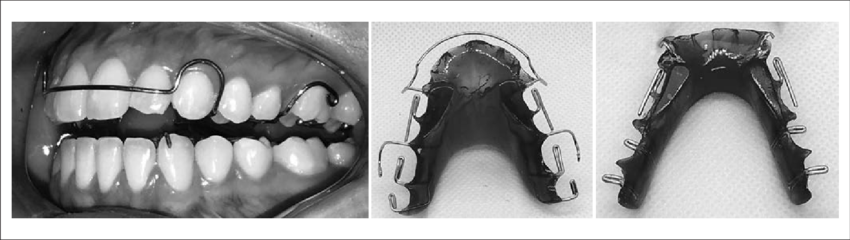

OG GATEKEPT FACEPULLING THREAD

Is poor nutrition, ignorant orthodontics, and bad karma creating a world of ugly, teeth-grinding, non-orgasmic beings who additionally end up suffering from TMJ and jaw pain? What if I told you that you could change your bad fortune in only 30 minutes a day while you watch TV - and that all this...

I tasted this shit and works well, i bring the helmet with my ortho, he aproved this shit and now he thinks im some kind of genius JFL (even when i said that this shit wasnt my idea), i will be updating of the results, right now im on orthopedics to improve nasal breathing (that shit is working crazy) and my ortho said that i need to wait 1.5 months to use the helmet, so imma wait.